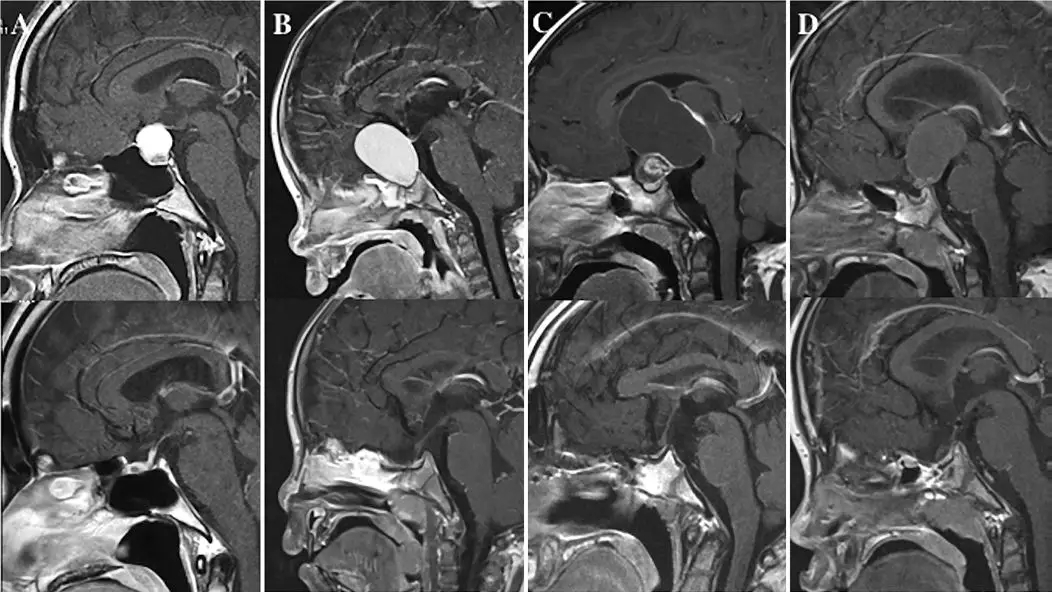

首诊时已播散的儿童中枢神经系统(CNS)肿瘤较罕见,关于其临床特征、治疗策略和预后分析等方面的文献很少。这类患者的外科治疗极富挑战性,尤其是脑积水的处理。作者分享了他们诊疗首诊时已播散的儿童CNS肿瘤的经验,并与局限性肿瘤进行比较。该研究回顾性分析了2003年至2016年儿童神经外科中心收治的361例患儿的临床资料,肿瘤首诊时已播散53例,肿瘤局限308例。纳入分析5类肿瘤:髓母细胞瘤(播散组29例,局限组74例)、原始神经外胚层肿瘤(PNET) (8例,17例),非典型畸胎样横纹肌样瘤(ATRT)(8例,22例),毛细胞星形细胞瘤(PA)(6例,138例)和室管膜瘤(2例,57例)。肿瘤播散患者和肿瘤局限患者的随访时间无明显差异(64.0vs74.5月)。综合分析上述5类肿瘤患者的数据,首诊时肿瘤已播散的患者脑脊液分流风险高,手术并发症多,肿瘤全切率低。多因素分析发现,没有任何因素可以预测脑室外引流(EVD)后是否需行永久性脑脊液分流术;两种分流术式VP分流和内镜下第三脑室造瘘术(ETV)比较,无明显差异。作者认为肿瘤类型和首诊时已播散是影响患儿预后的主要因素。儿童CNS肿瘤合并脑积水的处理富有挑战性,需要前瞻性研究进一步明确最佳分流方式。

髓母患儿首诊时(A-E)和5年后(F-J)复查的影像学资料